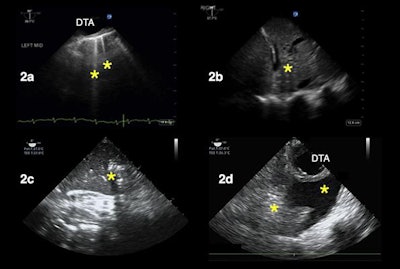

TEE can also be used to image patients' lungs from within their esophagus, also known as transesophageal lung ultrasound (TELUS). This version of lung ultrasound may work particularly well for certain types of patients, such as obese individuals, those with surgical dressing, or those experiencing subcutaneous emphysema, the authors noted.

Other use cases for TEE include evaluating the heart and lungs of patients who must stay in a prone position and those experiencing shock, a finding not uncommon in hospitalized patients with COVID-19, according to the authors.